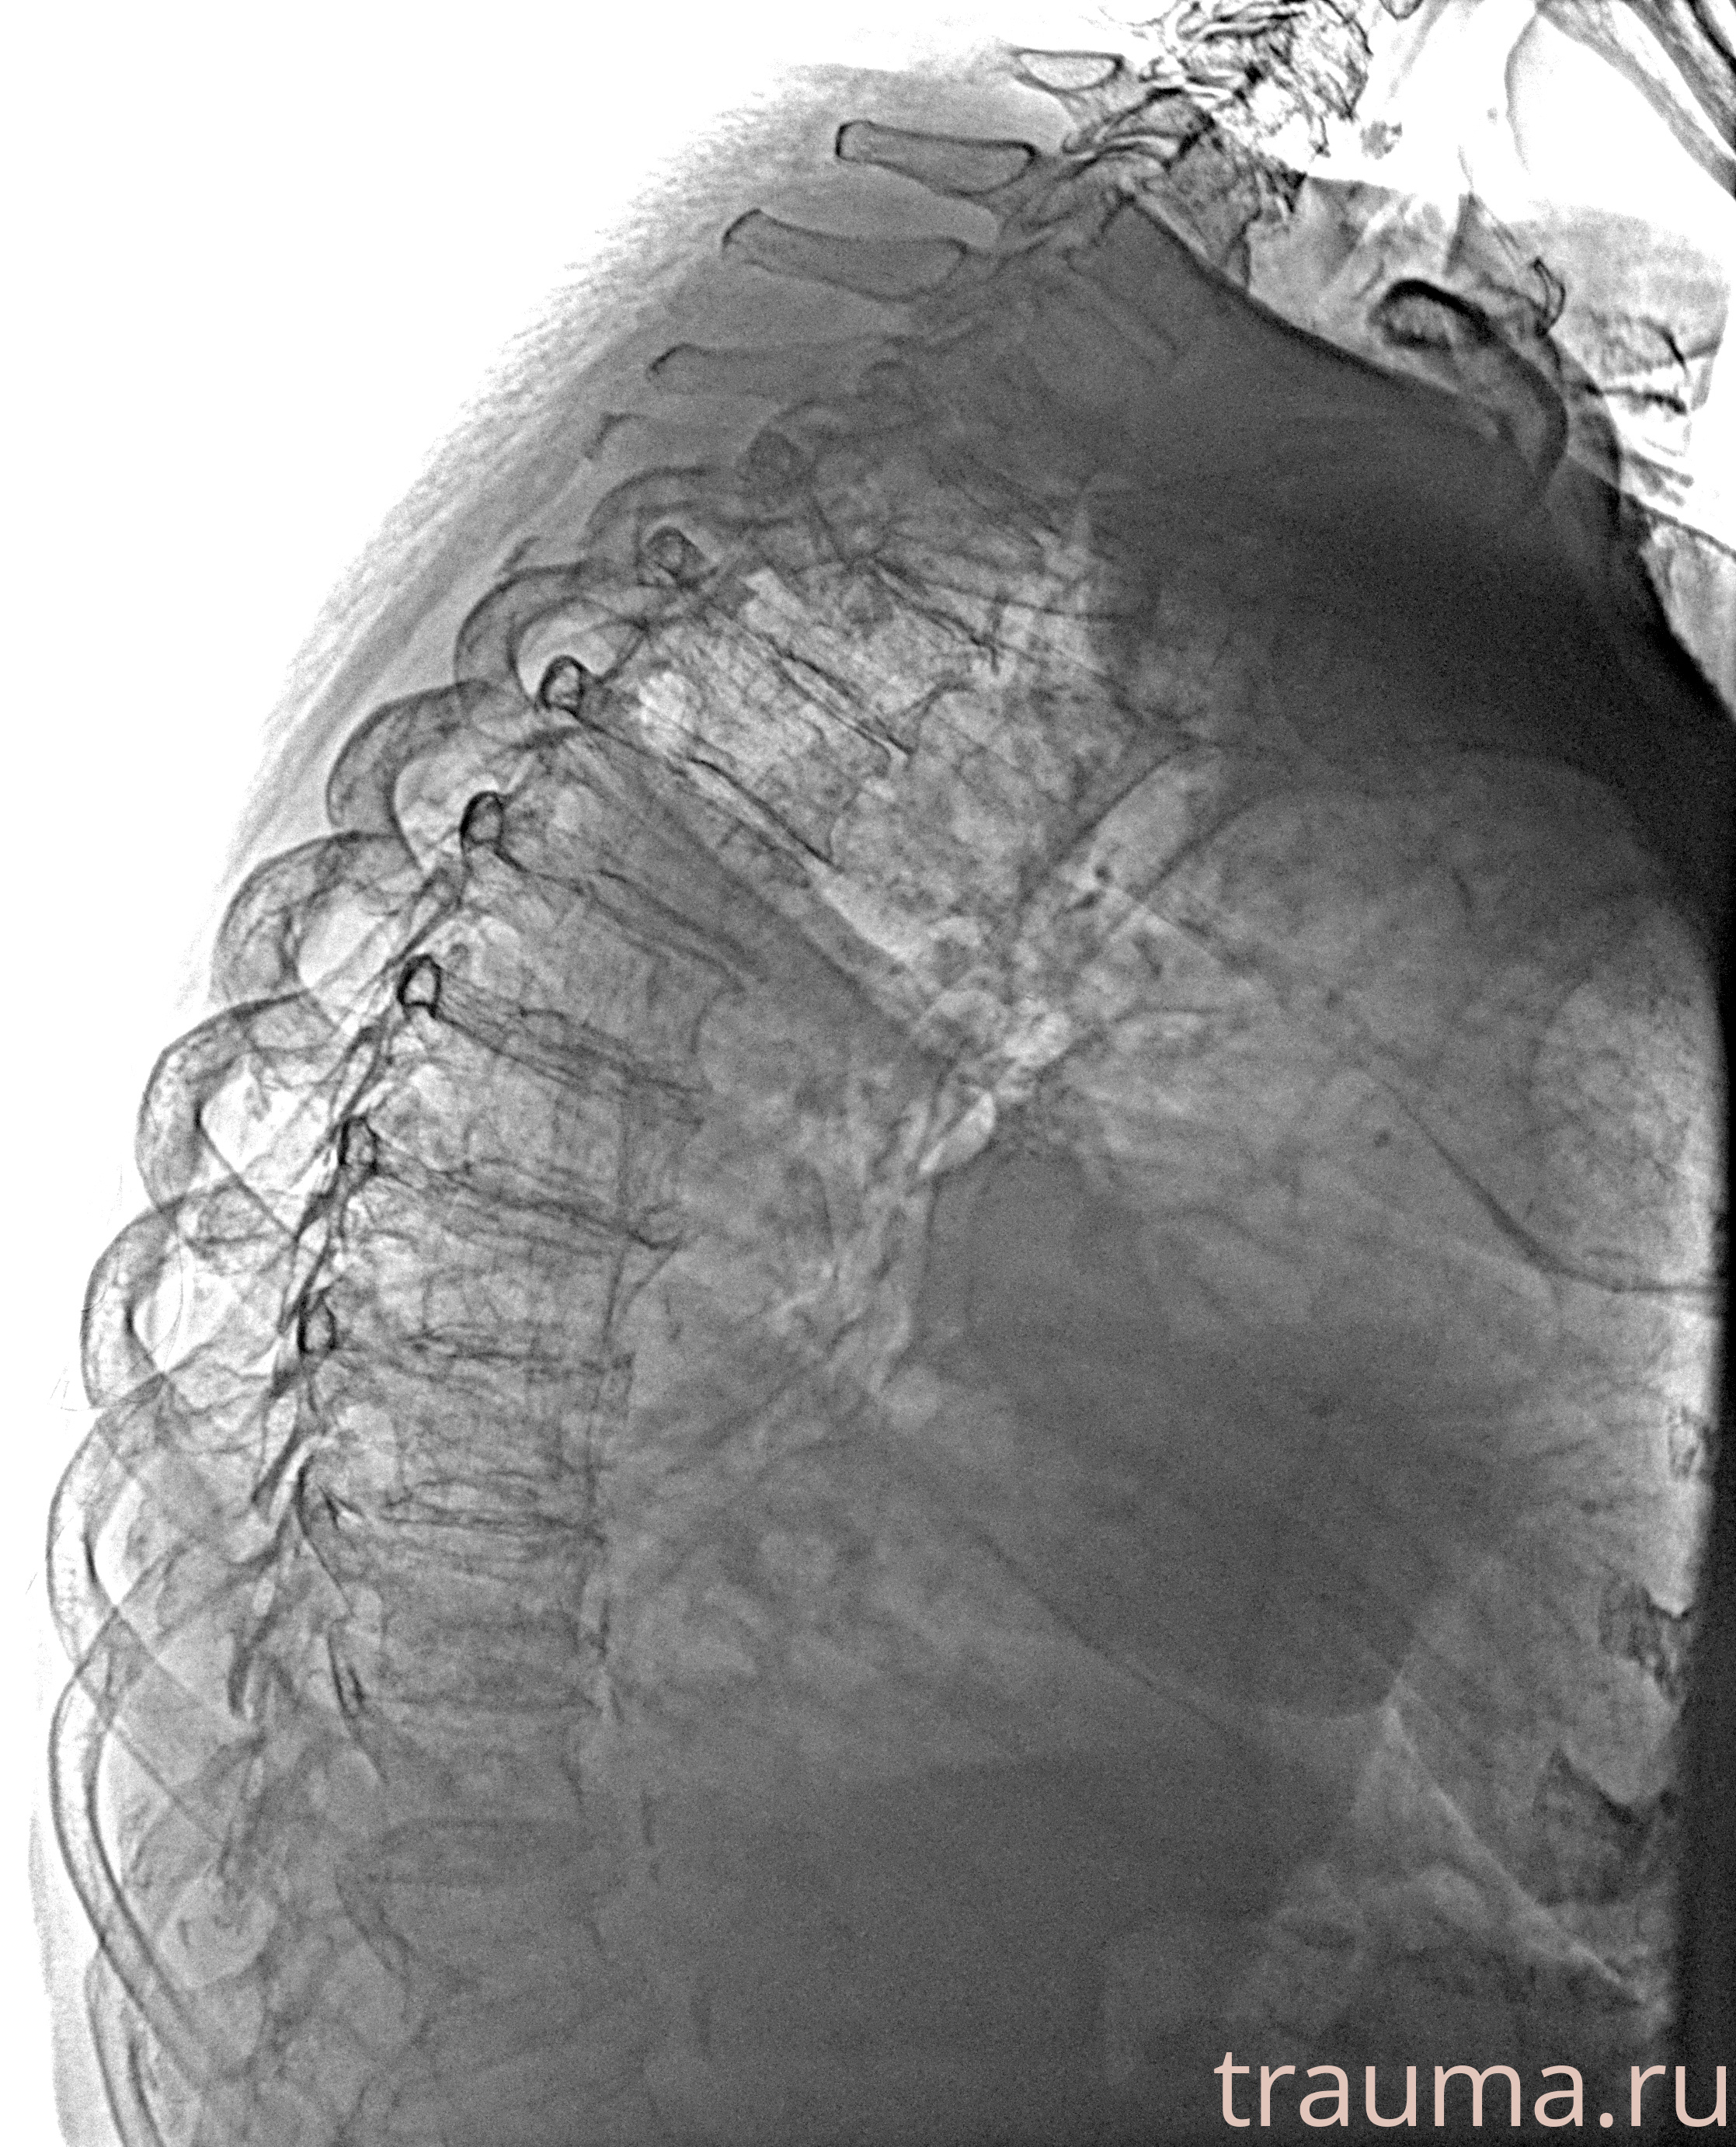

Рентгенограммы

Рентген на дому: по вашему адресу приезжает врач-рентгенолог, травматолог-ортопед с мобильным рентгеновским аппаратом, проводит диагностику травмы или заболевания, делает необходимые рентгенограммы, дает рекомендации по дальнейшему лечению. Получить качественные снимки в домашних условиях возможно благодаря уникальной методике, разработанной МосРентген Центром для института  Склифосовского

при переломе шейки бедра и пневмонии от компании МосРентген Центр - партнера Института имени Склифосовского